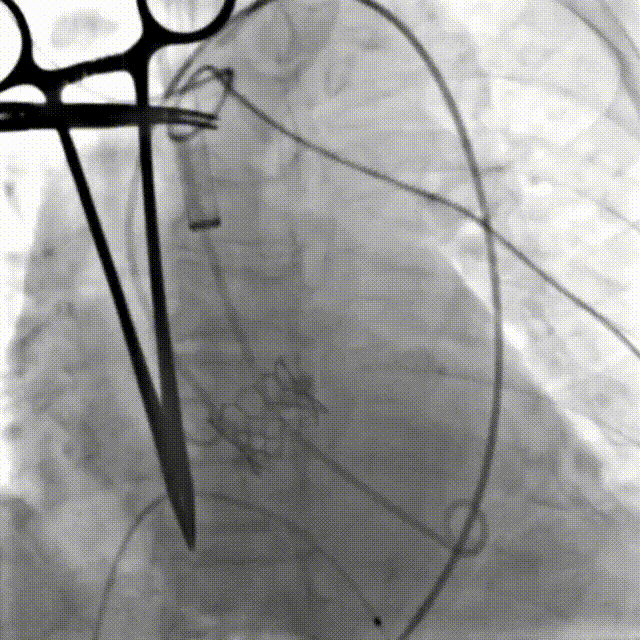

患者全麻后,游离颈动脉建立入路,主动脉根部造影显示主动脉瓣明显钙化伴重度狭窄。直头导丝跨瓣后,测得左心室、主动脉压力分别为180/-7mmHg,84/45mmHg。在180次/分快速心室起搏下,选择18mm球囊进行预扩张。根据术前评估及球囊预扩情况,最终选择23mm Prizvalve®球扩瓣进行植入,主动脉根部造影见轻微主动脉瓣反流,复查左心室、主动脉压力分别为151/1mmHg、150/72mmHg。术后即刻经食道超声心动图评估峰值流速1.4m/s,平均压差4mmHg,瓣口面积约2.1cm²,血流动力学指标理想。

瓣膜释放